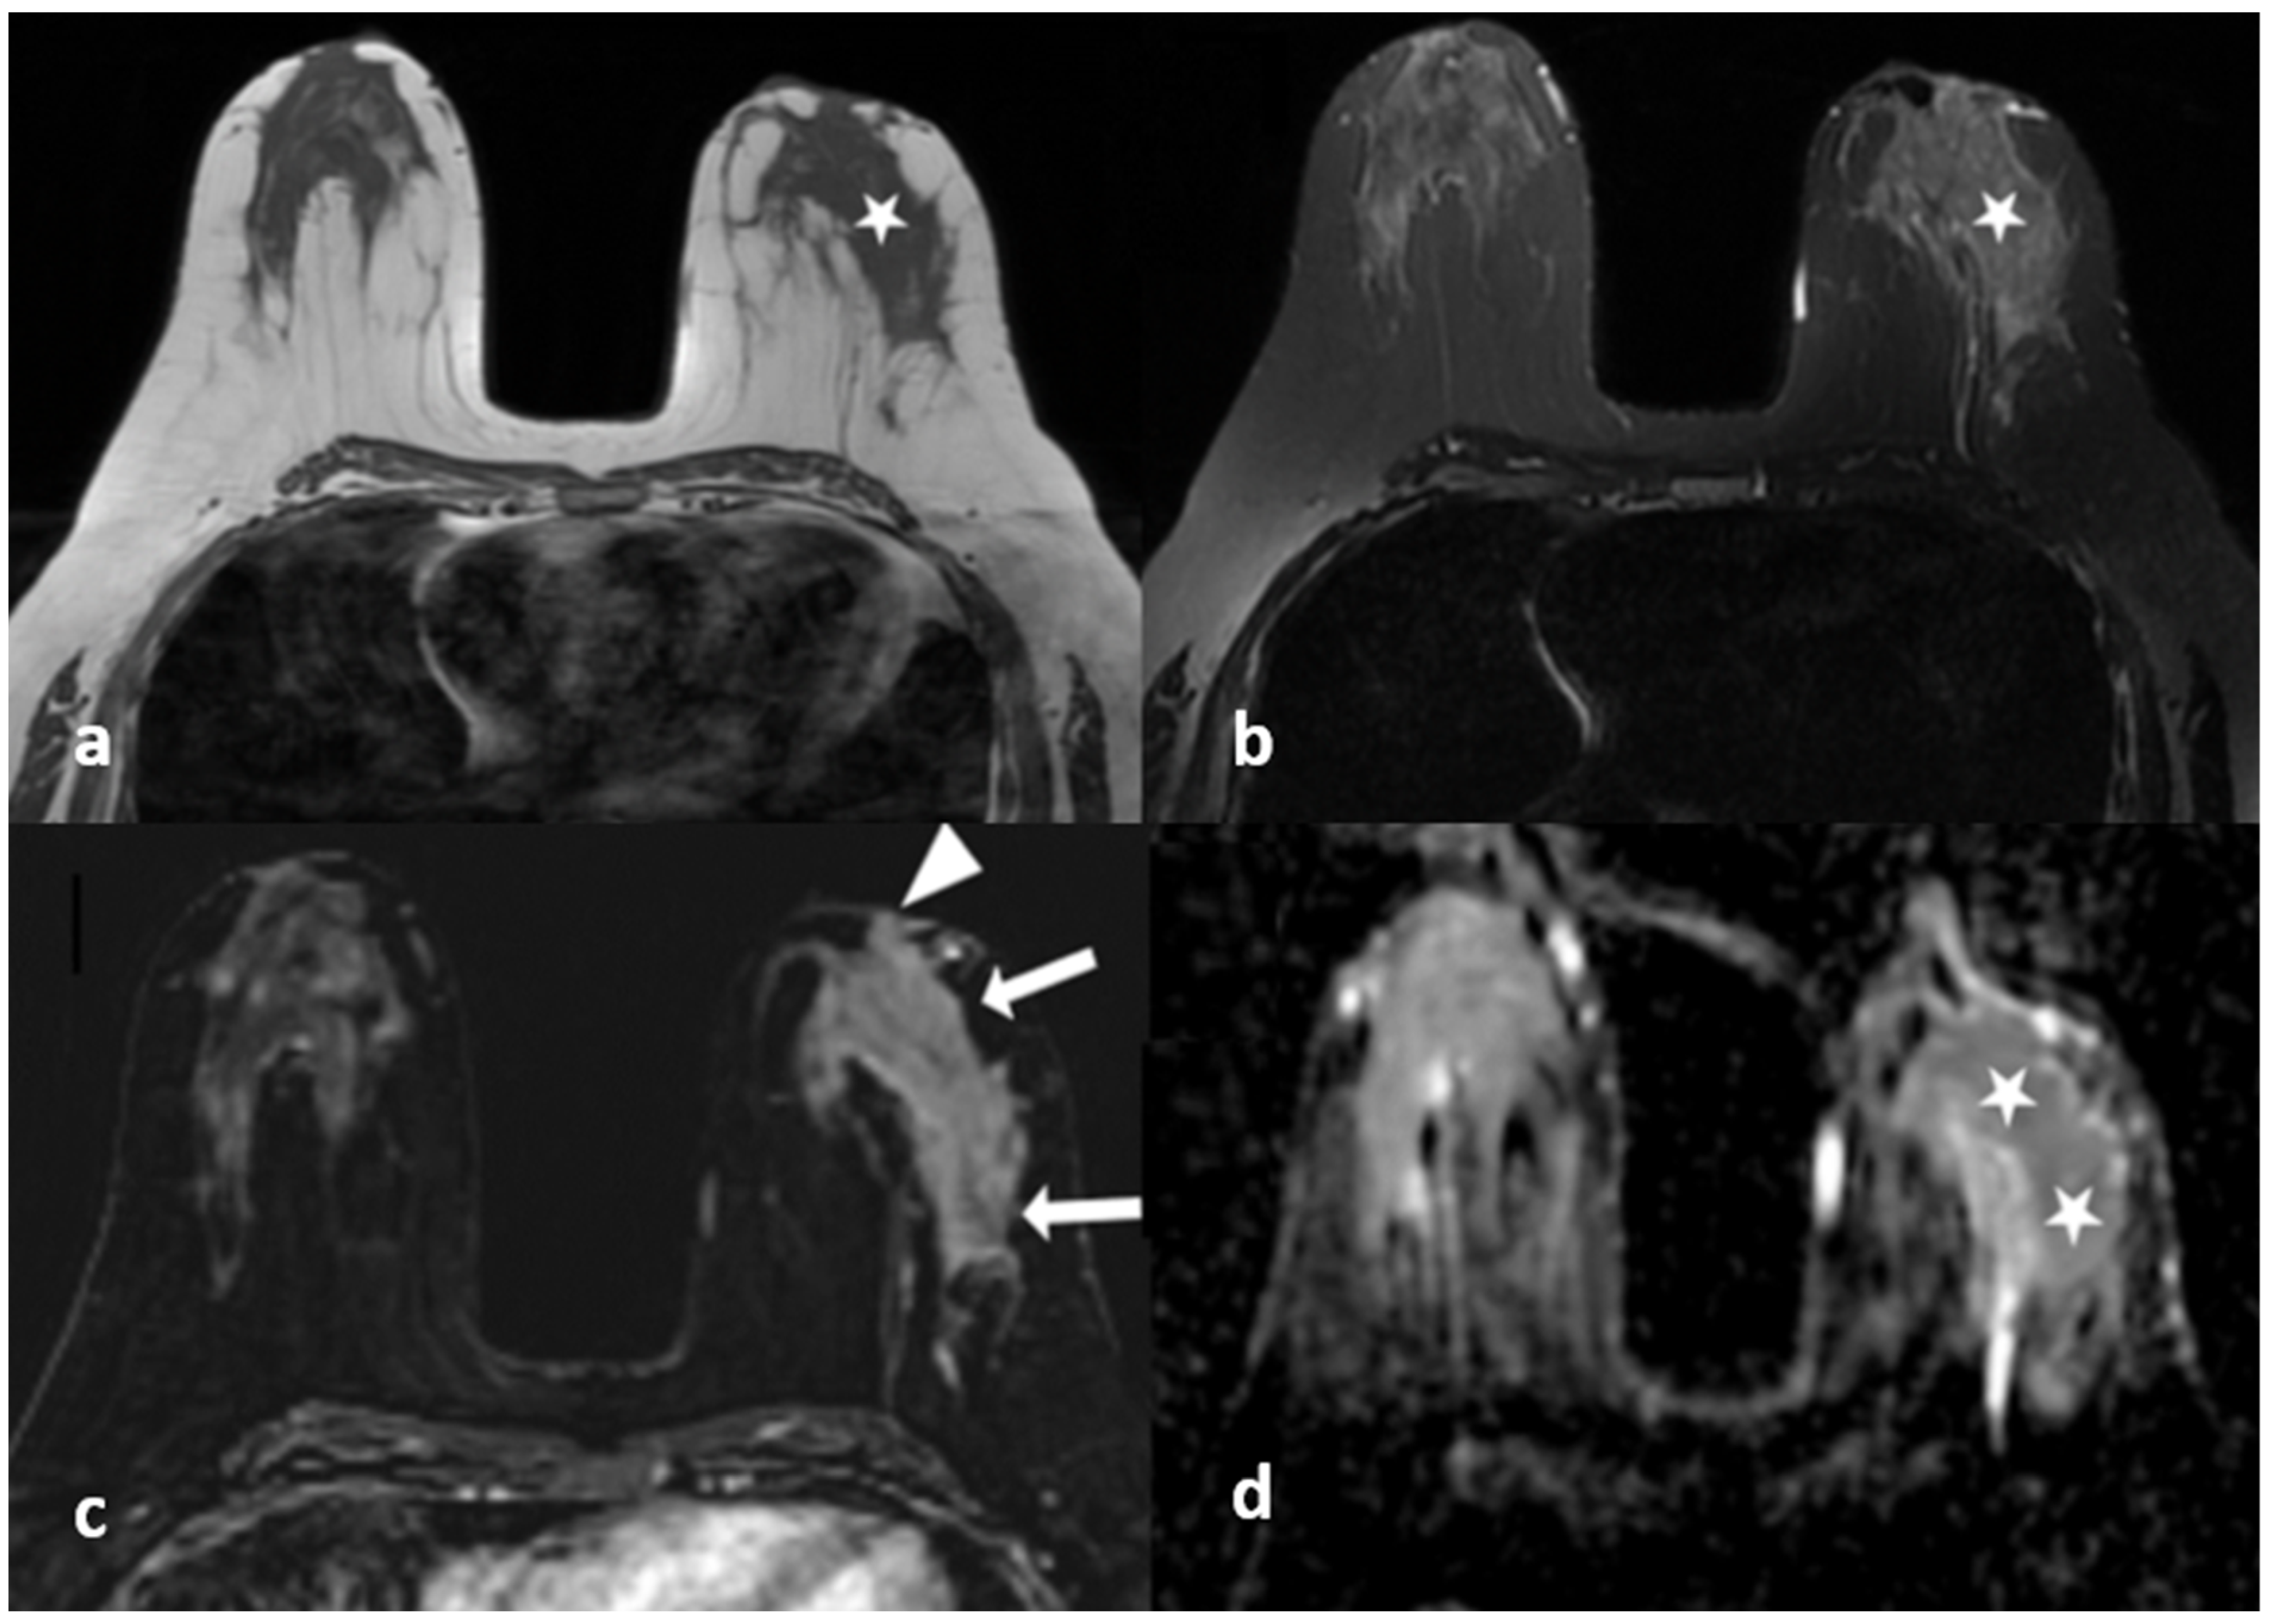

Figure 2.

(a–c) Fat containing dilated ducts (arrows) on fat-suppressed T2-weighted images in three different patients.

Figure 3.

A 45-year-old woman with histopathologically proven idiopathic granulomatous mastitis involving the right breast. (a) Precontrast T1-weighted fast spin echo axial MR image of the patient shows dilated ducts with a high signal intensity in retroareolar region (arrows). (b) Axial fat-saturated T2-weighted image corresponding to (a), which reveals that the dilated duct has a signal loss in accordance with the fat contained (arrows). (c) Contrast-enhanced subtracted image demonstrates a non-mass enhancement with a clustered ring pattern in the upper outer quadrant of the right breast (arrowhead). (d) T2-weighted fat-saturated image corresponding to (c) also demonstrates the dilated ducts containing fat intensity within the enhanced area (arrow).

Central location was mostly seen in IGM with a significant difference (p < 0.05) and an OR of 0.14 (0.02–0.74). Periareolar location was also significantly more common in IGM (p < 0.001) (Figure 4).

Figure 4.

A 40-year-old woman with histopathologically proven idiopathic granulomatous mastitis involving the left breast. (a) T1-weighted fast spin echo axial MR image of the patient shows mild parenchymal asymmetry in the upper outer quadrant of the left breast (star). (b) Axial fat-saturated T2-wieghted fast spin echo MR image, corresponding to (a), which reveals a moderate signal increase in the parencyma (star). (c) Axial contrast-enhanced subtracted image demonstrates a heterogeneous enhancement in the parenchyma (arrows) and a pathologic enhancement extending to the skin in the periareolar region (arrowhead). (d) ADC map at the same location shows a moderate signal decrease (stars) revealing restriction of diffusion in the area corresponding to (a–c).